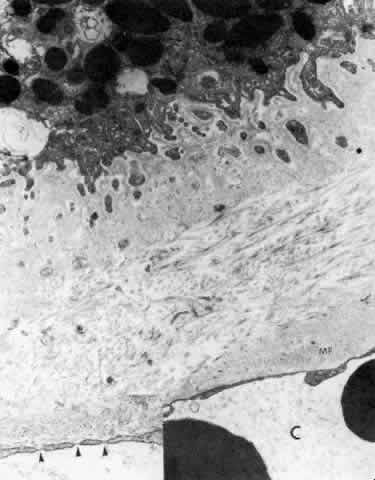

Fig. 27. Ciliary body stroma under the processes, anterior pars plicata. Even at

age 19, the basement membrane is thick. Collagen and other fine filaments

fill the narrow space between epithelium and fenestrated capillary

wall (C). Inset. Arrowheads indicate fenestrae in wall. Clumps of tubular

microfibrils (MF) of the elastic system are closely associated with

the capillary wall. (X 17,300; inset, X 43,000) Fig. 27. Ciliary body stroma under the processes, anterior pars plicata. Even at

age 19, the basement membrane is thick. Collagen and other fine filaments

fill the narrow space between epithelium and fenestrated capillary

wall (C). Inset. Arrowheads indicate fenestrae in wall. Clumps of tubular

microfibrils (MF) of the elastic system are closely associated with

the capillary wall. (X 17,300; inset, X 43,000)

|